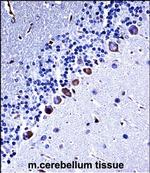

CK1 gamma Polyclonal Antibody

Mouse

Rabbit Polyclonal

WB IHC (P) Flow

货号 PA5-71858

CK1 gamma-3 Polyclonal Antibody

Human Mouse Rat

WB IHC (P)

货号 PA5-99838